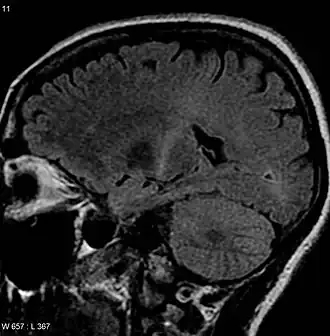

| Uma MRI com sinal aumentado na parte posterior da cápsula interna que pode rastrear o córtex motor que é consistente com o diagnóstico de ELA | |